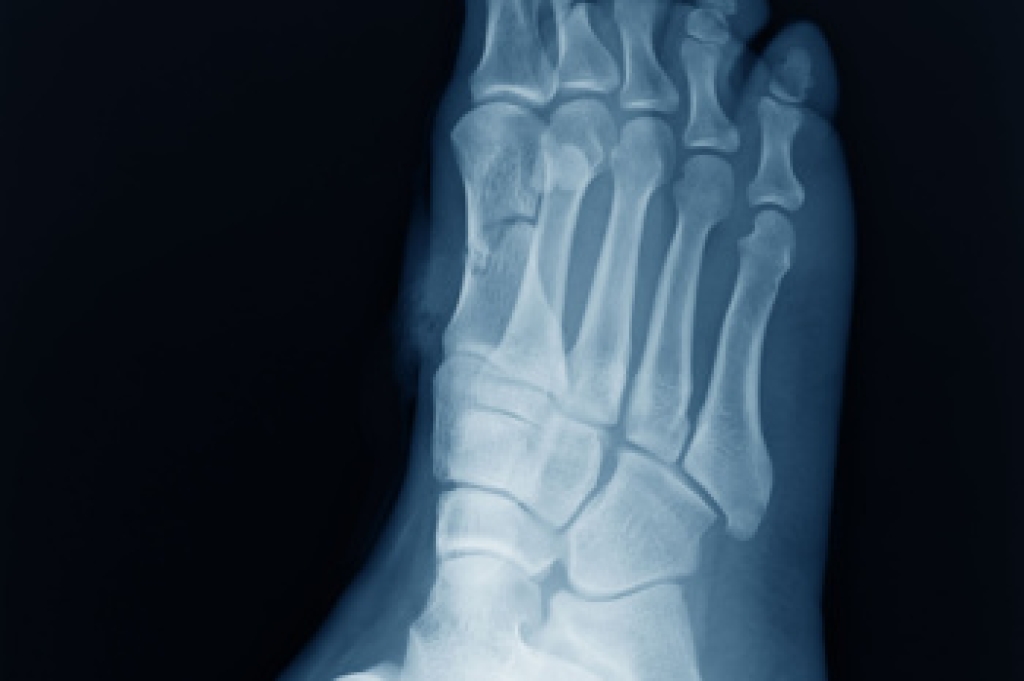

The foot is a complex weight-bearing structure made of bones, joints, tendons and ligaments that work together to support standing, walking and running. Key bones include the talus, which connects the foot to the ankle, the calcaneus which forms the heel, and the navicular, cuboid, and the cuneiforms that create the arch and midfoot stability. These bones form joints that allow smooth coordinated motion while tendons attach muscles to bone to generate movement. Ligaments provide stability by holding the bones in proper alignment. Together they absorb shock, adapt to uneven surfaces and propel the body forward. A podiatrist can evaluate biomechanical function, treat pain, and prevent injury. If you have foot or ankle pain, it is suggested that you consult a podiatrist who can offer effective treatment solutions, and expert tips on how to maintain strong, healthy feet.

Podiatric biomechanics is a particular sector of specialty podiatry with licensed practitioners who are trained to diagnose and treat conditions affecting the foot, ankle and lower leg. Biomechanics deals with the forces that act against the body, causing an interference with the biological structures. It focuses on the movement of the ankle, the foot and the forces that interact with them.